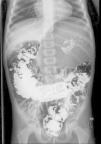

El segundo caso es un niño de 3 años de edad, que fue atendido en urgencias por episodios diarios de molestias y distensión abdominal intermitente de 2 meses de evolución, asociándose a vómitos alimenticios. En la exploración únicamente se observaba distensión de hemiabdomen superior con timpanismo importante. Ante la sospecha se decidió realizar radiografía de abdomen (fig. 2) que confirmó la existencia de vólvulo gástrico. Se introduce sonda nasogástrica y se realizó gastrofrenopexia y gastropexia anterior laparoscópica. Posteriormente, presentó buena evolución.

El diagnóstico suele realizarse mediante la radiografía de abdomen y un tránsito esófago-gastro-duodenal3 aunque a veces estas pueden ser normales4. Por ello, se deberá recurrir a otras técnicas de imagen como la TAC si la sospecha clínica es alta y las pruebas anteriormente mencionadas son normales. Según el eje sobre el que se produzca el giro del estómago, el vólvulo será órgano-axial (54% de los agudos y 85% de los crónicos)1, mesentérico-axial (41% de los agudos y 10% de los crónicos)1 o mixto5. Los hallazgos incluirían distensión masiva, posición anómala gástrica, dos imágenes de niveles hidroaéreos, «pico de ave» en la unión esofagogástrica, etc. En el órgano-axial el estómago tiene plano horizontal con la curvatura mayor superior a la menor. En el mesentérico-axial la unión antroduodenal está encima de la gastroesofágica y el plano gástrico es vertical, con forma esférica.